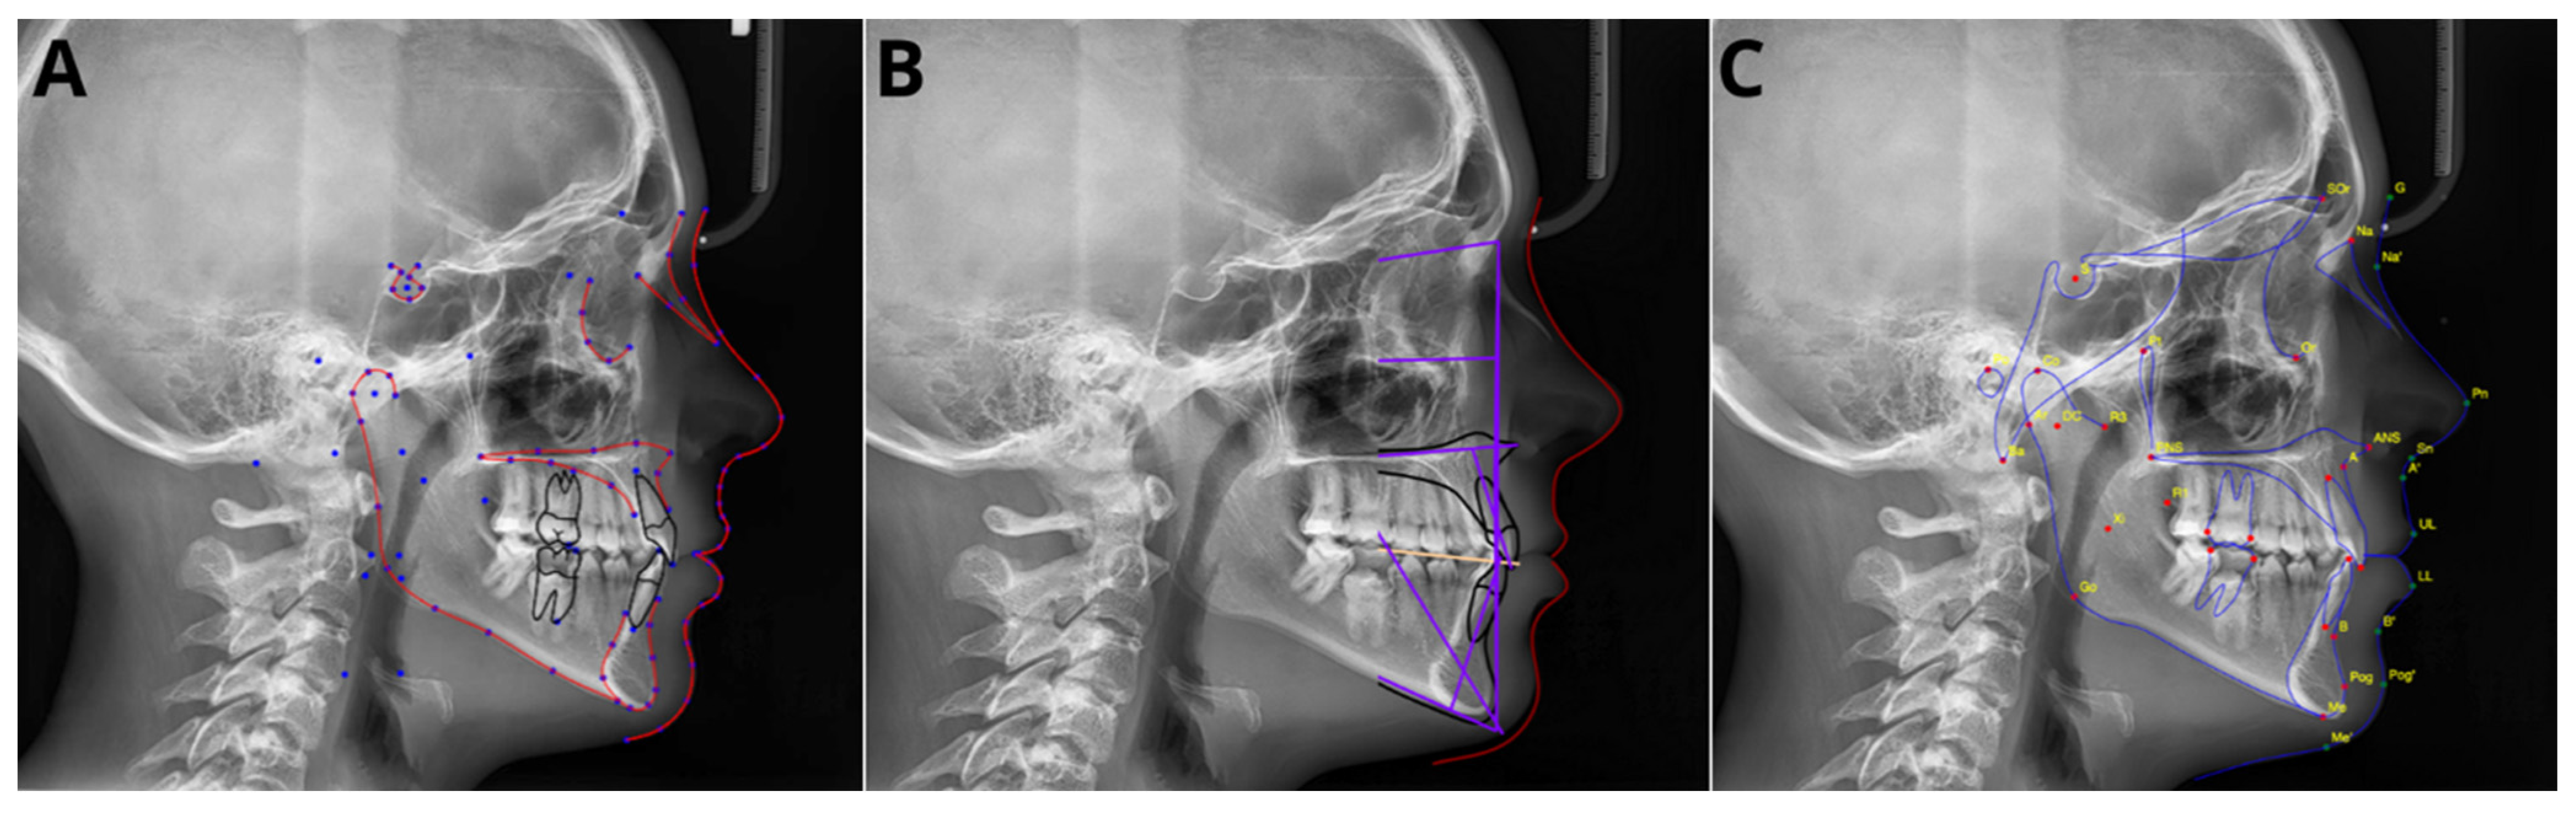

2.3. Automatic Cephalometric Analysis